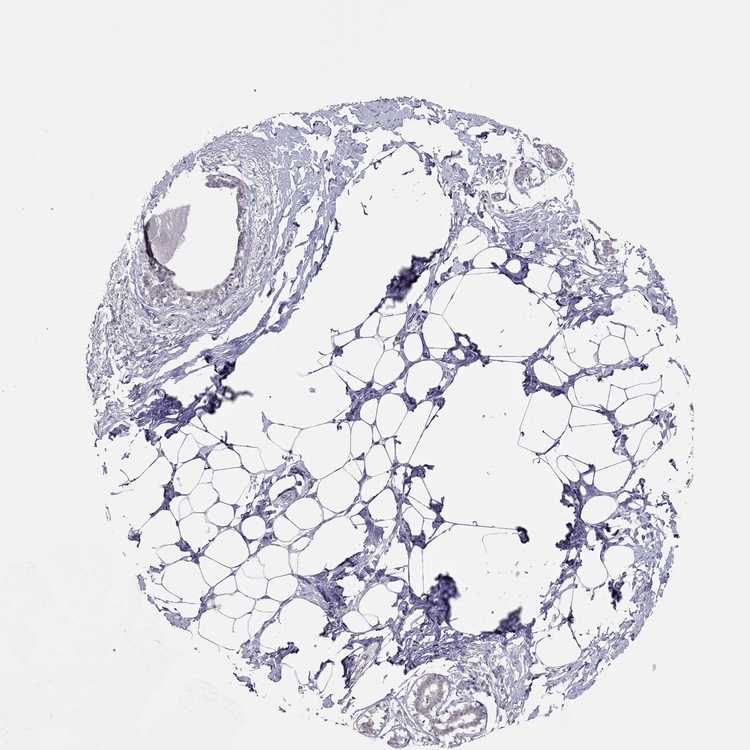

TISSUE PRIMARY DATA BREAST Show tissue menu

BREAST - Antibody stainingi

Antibody staining in the annotated cell types in the current human tissue is reported as not detected, low, medium, or high, based on conventional immunohistochemistry profiling in selected tissues. This score is based on the combination of the staining intensity and fraction of stained cells.

Each image is clickable and will lead to virtual microscopy that enables deeper exploration of all samples and also displays staining intensity scores, fraction scores and subcellular localization as well as patient and tissue information for each sample.

Antibody HPA075775

Adipocytes Not detected

Glandular cells Not detected

Myoepithelial cells Not detected